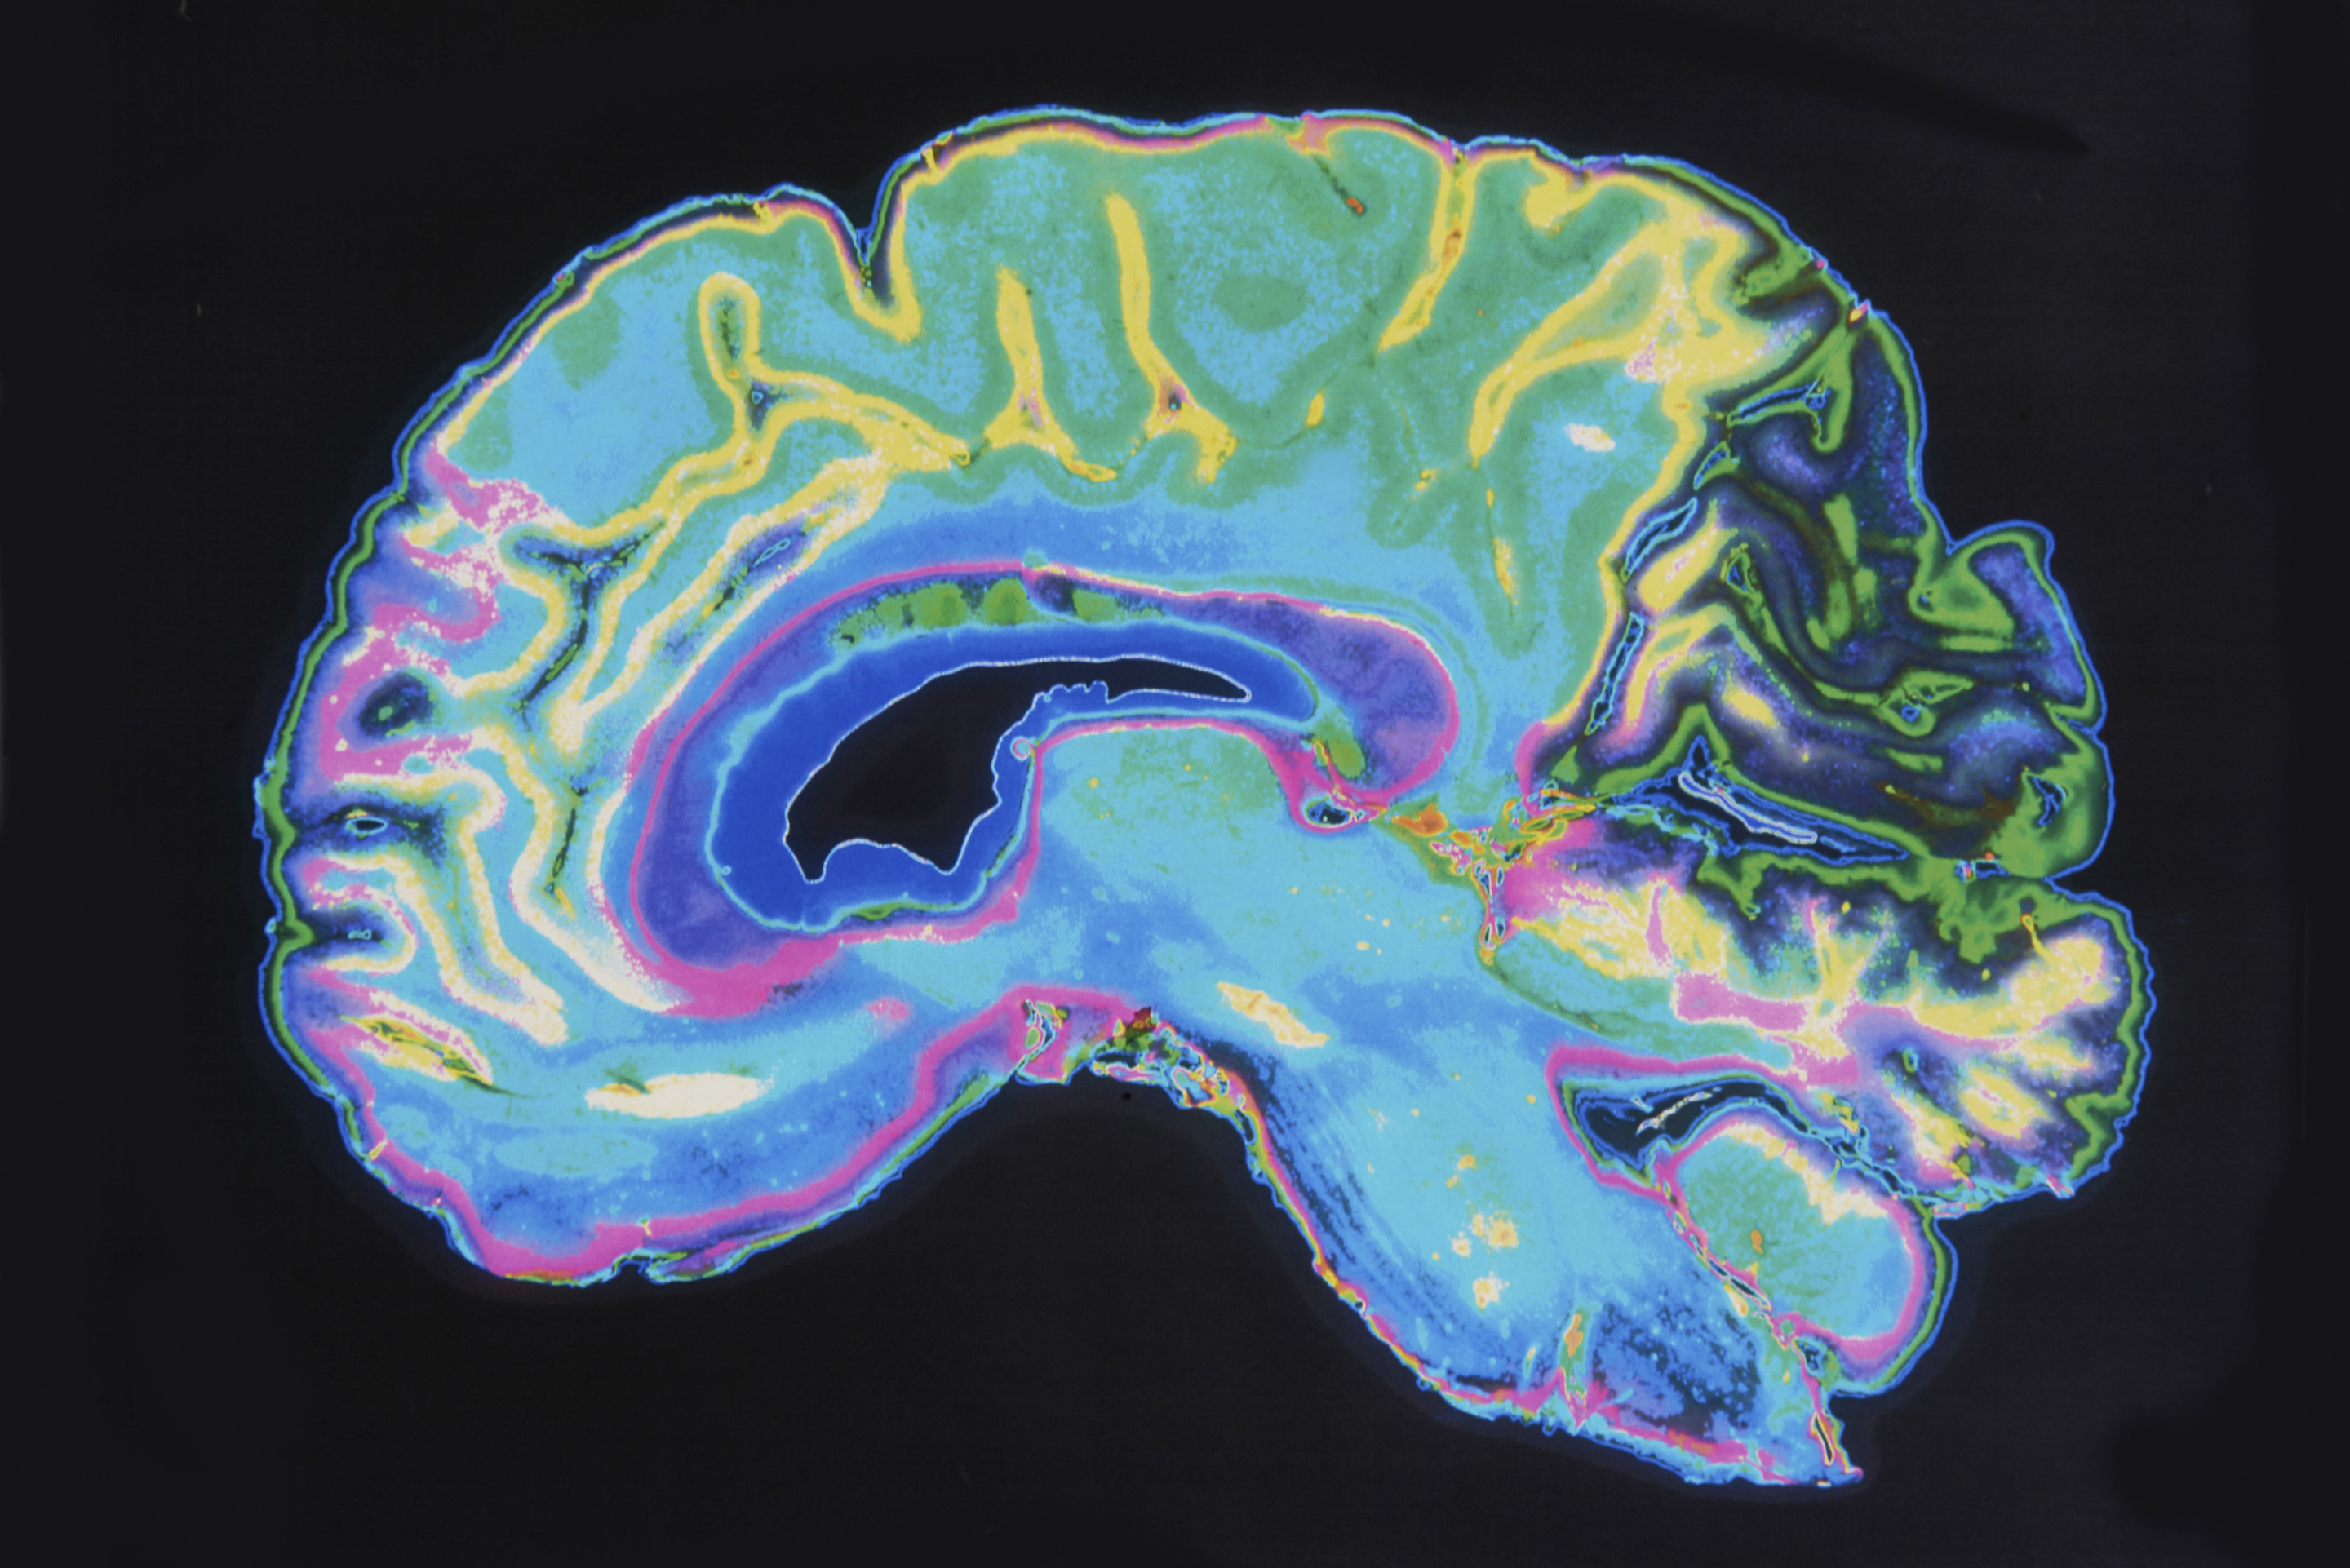

That could change as deep brain stimulation (DBS) goes from a way to treat motor diseases to a possible treatment for chronic pain – treatment that can be customized to the patient’s brain makeup and their own brain’s feedback.

DBS already is used to treat movement disorders, like Parkinson’s disease, dystonia and essential tremors. Patients have electrodes implanted deep into the parts of their brain that control movement, and receive electrical current via a stimulator put into their chest.

Instead of providing a continuous current, this grant is helping researchers make the electric charge more customized by first identifying new targets for stimulation, and creating systems that can take feedback from the brain and adjust the device accordingly.

“When we find those new targets, the next goal is identifying brain biomarkers of chronic pain for each patient,” Shirvalkar said. That means recording direct from patients’ brains while they experience natural pain fluctuations. “By combining their neural signals with their pain reports, we’re trying to build a model of how their brain represents pain.”